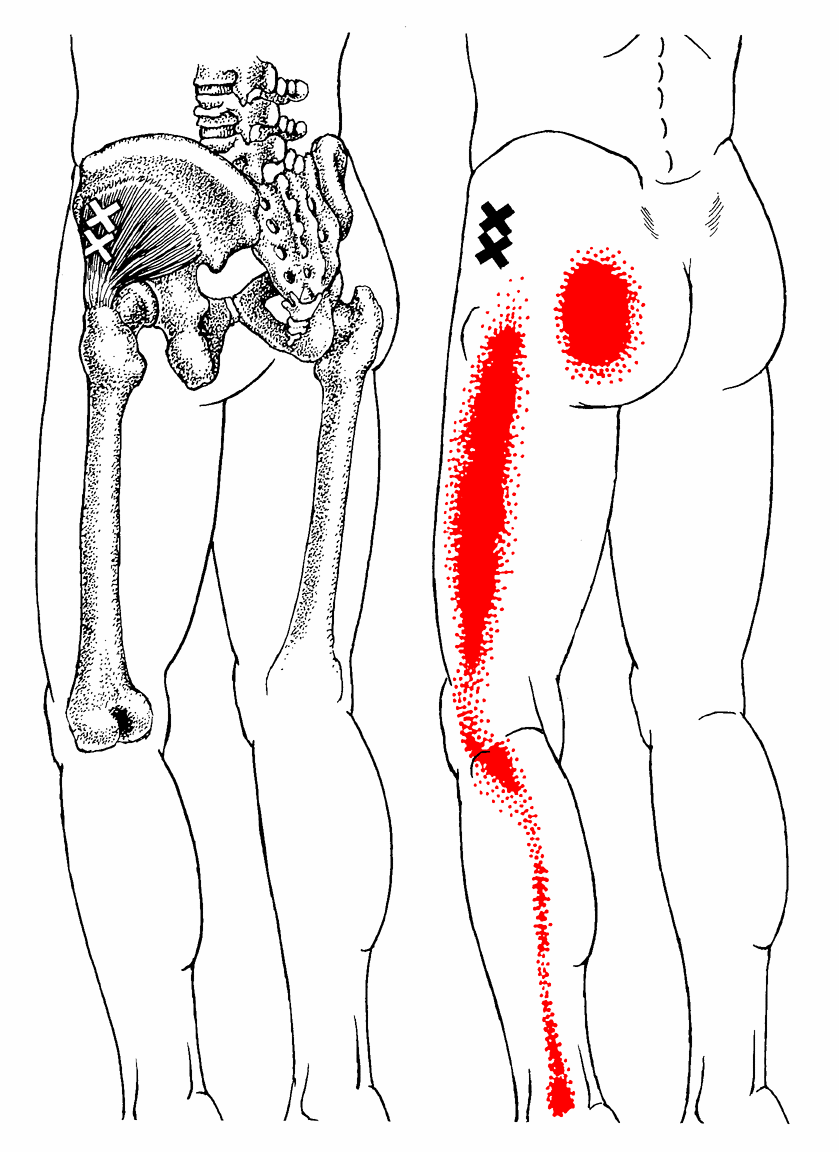

Ant.

Post. 소둔근의 Anterior part에 있는 TrPs에서의 방사통은 둔부 하외측 위와, 밑으로 대퇴의 측면, 무릎, 장딴지 및 발목으로 방사됩니다. Posterior fibers에 있는 trPs는 유사하지만 둔부의 하내측과 대퇴와 장딴지의 뒷 부분등 보다 후방으로 통증을 방사하는 경향을 갖습니다.

통증은 매우 고통스럽고 지속적인 양상으로 나타나며, TrPs의 위치가 깊이 위치하고 있고 원인 근육에서 매우 멀리 떨어진 곳에 통증이 나타나 TrPs를 찾기 어려운 경우가 많습니다.

앉아있을 때 보다 서있을 때 통증이 심화되는 경우가 많습니다.